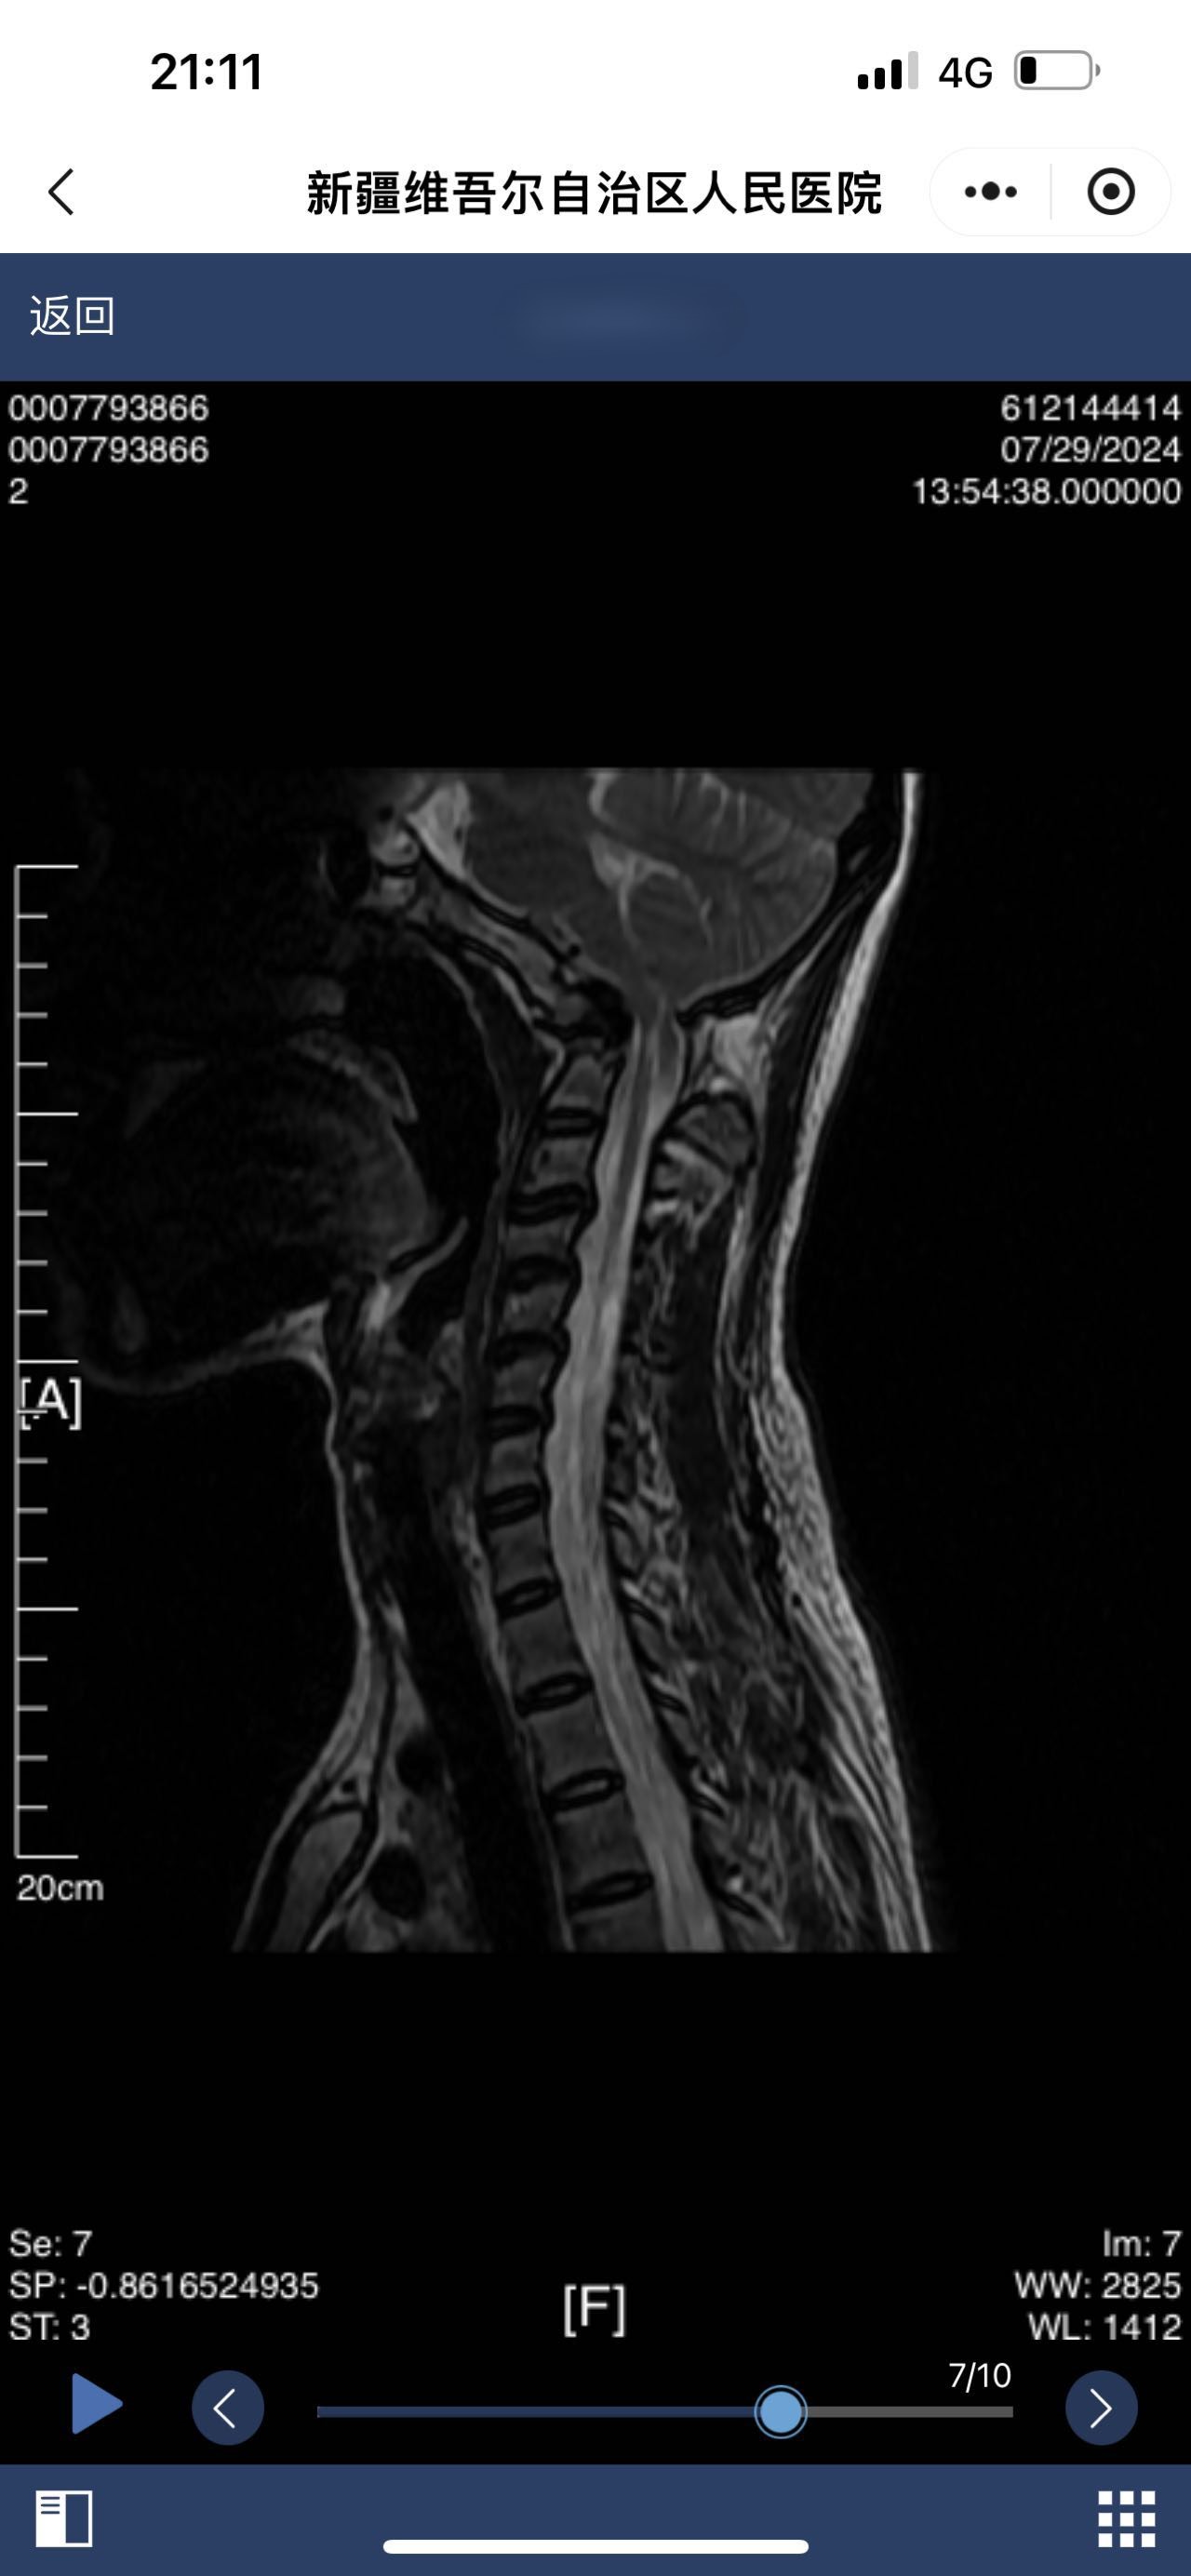

• 诊断:颅底凹陷

• 影像: